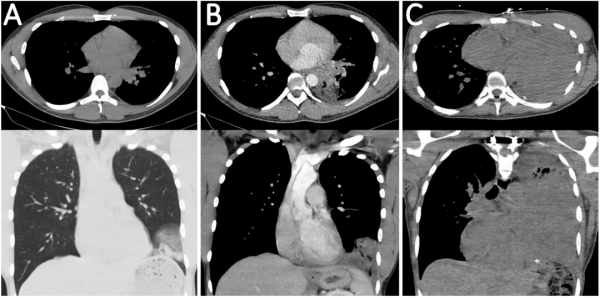

随后医生为A先生完善了辅助检查。血化验报告提示仅有轻度贫血,其他正常。胸部CT显示左下肺有一个大小3.4×4.4公分的阴影,周围是磨玻璃样改变,右肺存在直径最大0.3公分的散在实性结节(图1A)。结合病史,磨玻璃阴影可能和出血有关,A先生首先接受了抗感染和对症治疗。

治疗的疗效如何?阴影究竟是不是炎症呢?一个月后,A先生再次到门诊随访胸部CT。他的咯血症状确实好转,磨玻璃样阴影消散了,但此时胸部CT上却看到了磨玻璃改变下的肿块影—阴影面积增大至4.9×4.2公分;此外,CT还显示A先生的第7胸椎(T7) 出现溶解性病变,右锁骨上、右气管上段和隆突下淋巴结肿大(图1B)。

图1. A先生首次就诊(A)、4周后(B)、20周后(C)的胸部CT表现

A先生的临床状况进一步恶化,出现了进行性发展的呼吸困难、再次出现了咯血以及顽固性背痛。后续随访胸部CT,他的左肺几乎被肿瘤所占据,在影像学上已经不能正常显示(图1C)。医生尝试二线化疗但效果不理想,病情进一步发展,A先生出现了呼吸衰竭和感染性休克,在初诊后不到半年(出现症状后5.8个月,确诊后4.7个月),A先生不幸离开了。